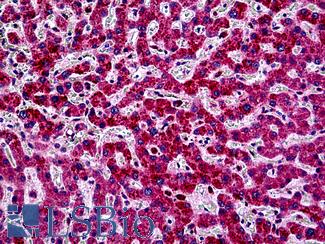

ACPP (PSAP)

Anti-Prostatic Acid Phosphatase antibody IHC of human prostate. Immunohistochemistry of formalin-fixed, paraffin-embedded tissue after heat-induced antigen retrieval. Antibody LS-B3108 concentration 5 ug/ml.